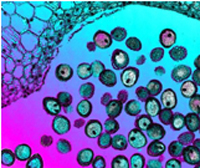

Researchers have made a variety of advances in their ability to image microscopic objects by using algorithms that produce sharper images than would normally be possible with any given optics, as well as by using techniques such as photo-acoustic imaging that combine optical absorption and ultrasonic waves to look at specific features inside living tissues.

The workshop, which will start on May 31, 2012 at NIST’s laboratories in Gaithersburg, will explore how such microscopy techniques can be used in tissue engineering and regenerative medicine.